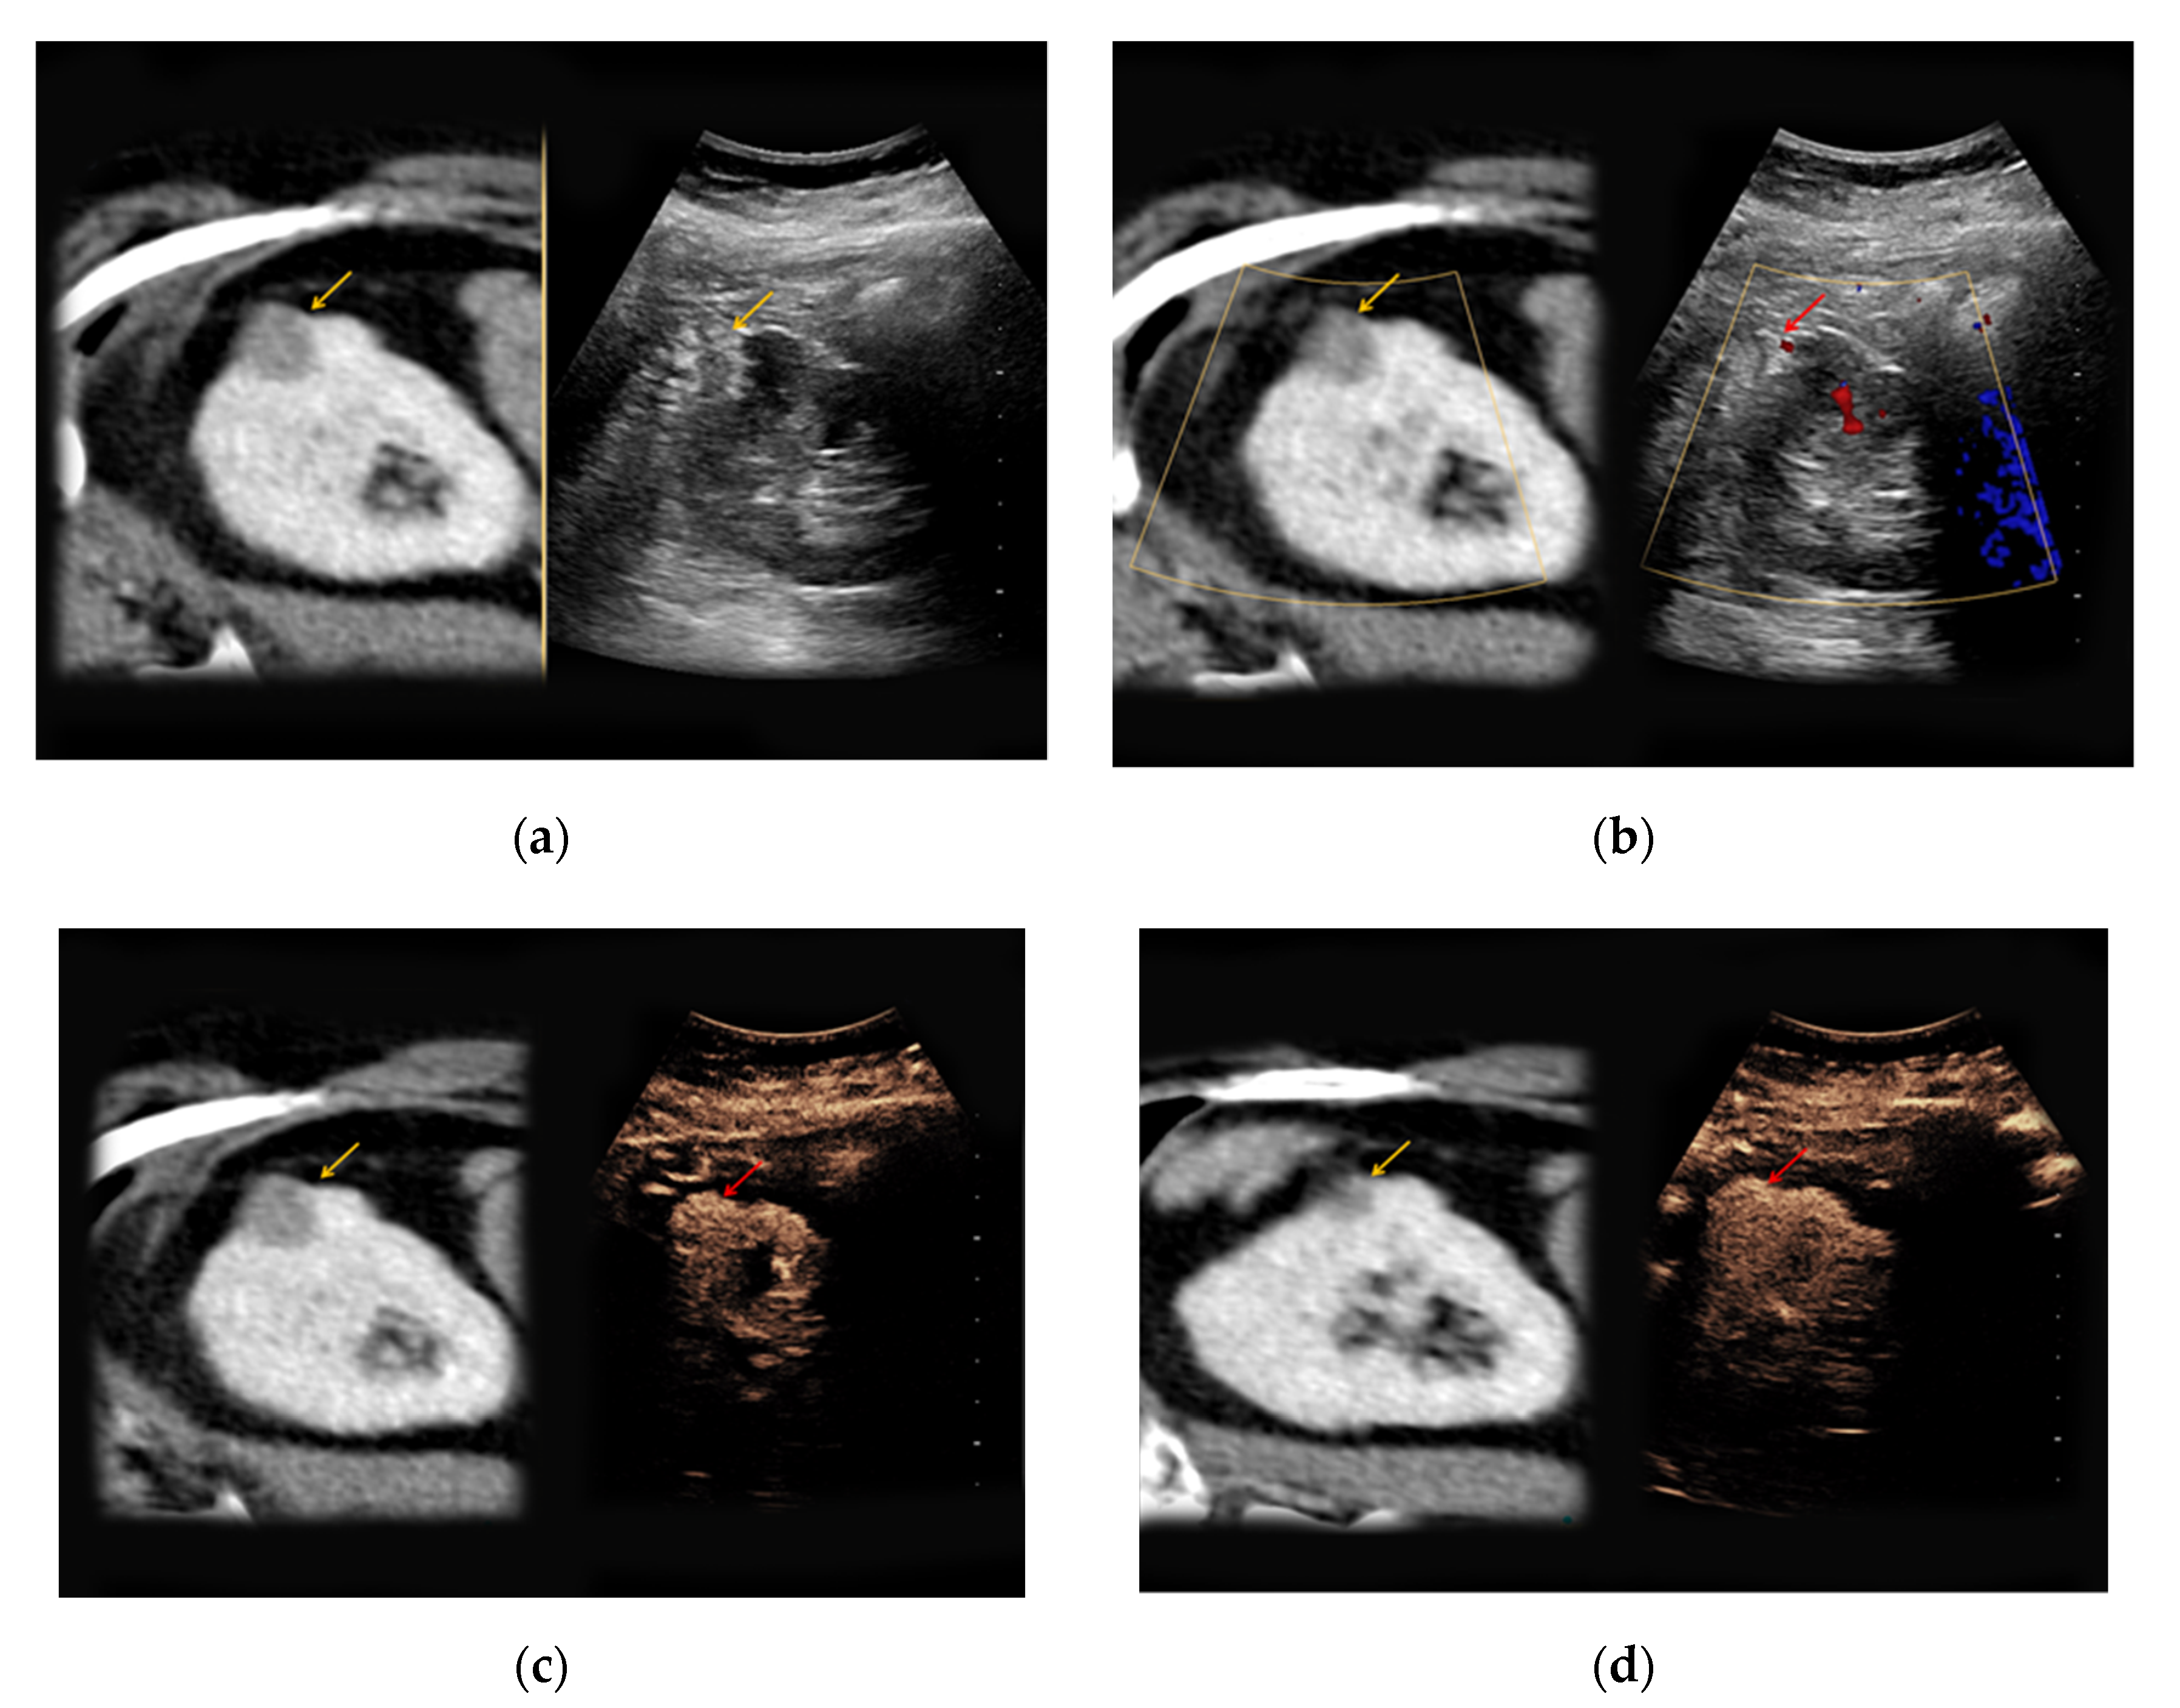

Figure 2. An 81-year-old patient with an unclear lesion in the right kidney incidentally detected in contrast-enhanced computed tomography (CT). (a) In native B-mode, an inhomogeneously hyperechoic lesion with a diameter of 2.5 cm could be registered (right picture, yellow arrow). In the corresponding contrast-enhanced CT scan (a, left picture, yellow arrow), the lesion presents hypodense with only low contrast-enhancement; (b) no major vascularization could be visualized in Doppler mode (right picture, red arrow). (c) CEUS shows a rapid hyperenhancement of the lesion (right picture, red arrow); (d) no wash-out in the late phase was registered (right picture, red arrow). The patient underwent partial nephrectomy, the results of the histopathological analysis revealed benign renal angiomyolipoma.

In 4/7 patients with confirmed angiomyolipoma, the lesions presented as hypoechoic in native B-mode (57%) and in 3/7 patients as hyperechoic (43%). Only one lesion showed slight hypervascularization in Doppler mode (14%). All lesions showed rapid contrast-enhancement (100%) (Figure 2), whereas only two lesions also showed venous wash-out (29%).